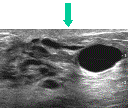

Ultrasound Imaging

Cyst